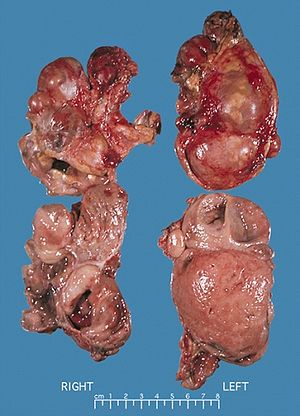

Bilateral pheochromocytomas associated with Multiple endocrine neoplasia type 2

Pheochromocytoma occurs in 33-50% of MEN2 cases.[5] In MEN2A, primary hyperparathyroidism occurs in 10–50% of cases and is usually diagnosed after the third decade of life. Rarely, it may present in childhood or be the sole clinical manifestation of this syndrome.[citation needed]MEN2A associates medullary thyroid carcinoma with pheochromocytoma in about 20–50% of cases and with primary hyperparathyroidism in 5–20% of cases.[citation needed] MEN2B associates medullary thyroid carcinoma with pheochromocytoma in 50% of cases, with marfanoid habitus and with mucosal and digestive neurofibromatosis.[citation needed]

In familial isolated medullary thyroid carcinoma the other components of the disease are absent.[citation needed] In a review of 85 patients 70 had MEN2A and 15 had MEN2B.[5] The initial manifestation of MEN2 was medullary thyroid carcinoma in 60% of patients, medullary thyroid carcinoma synchronous with pheochromocytoma in 34% and pheochromocytoma alone in 6%. 72% had bilateral pheochromocytomas.